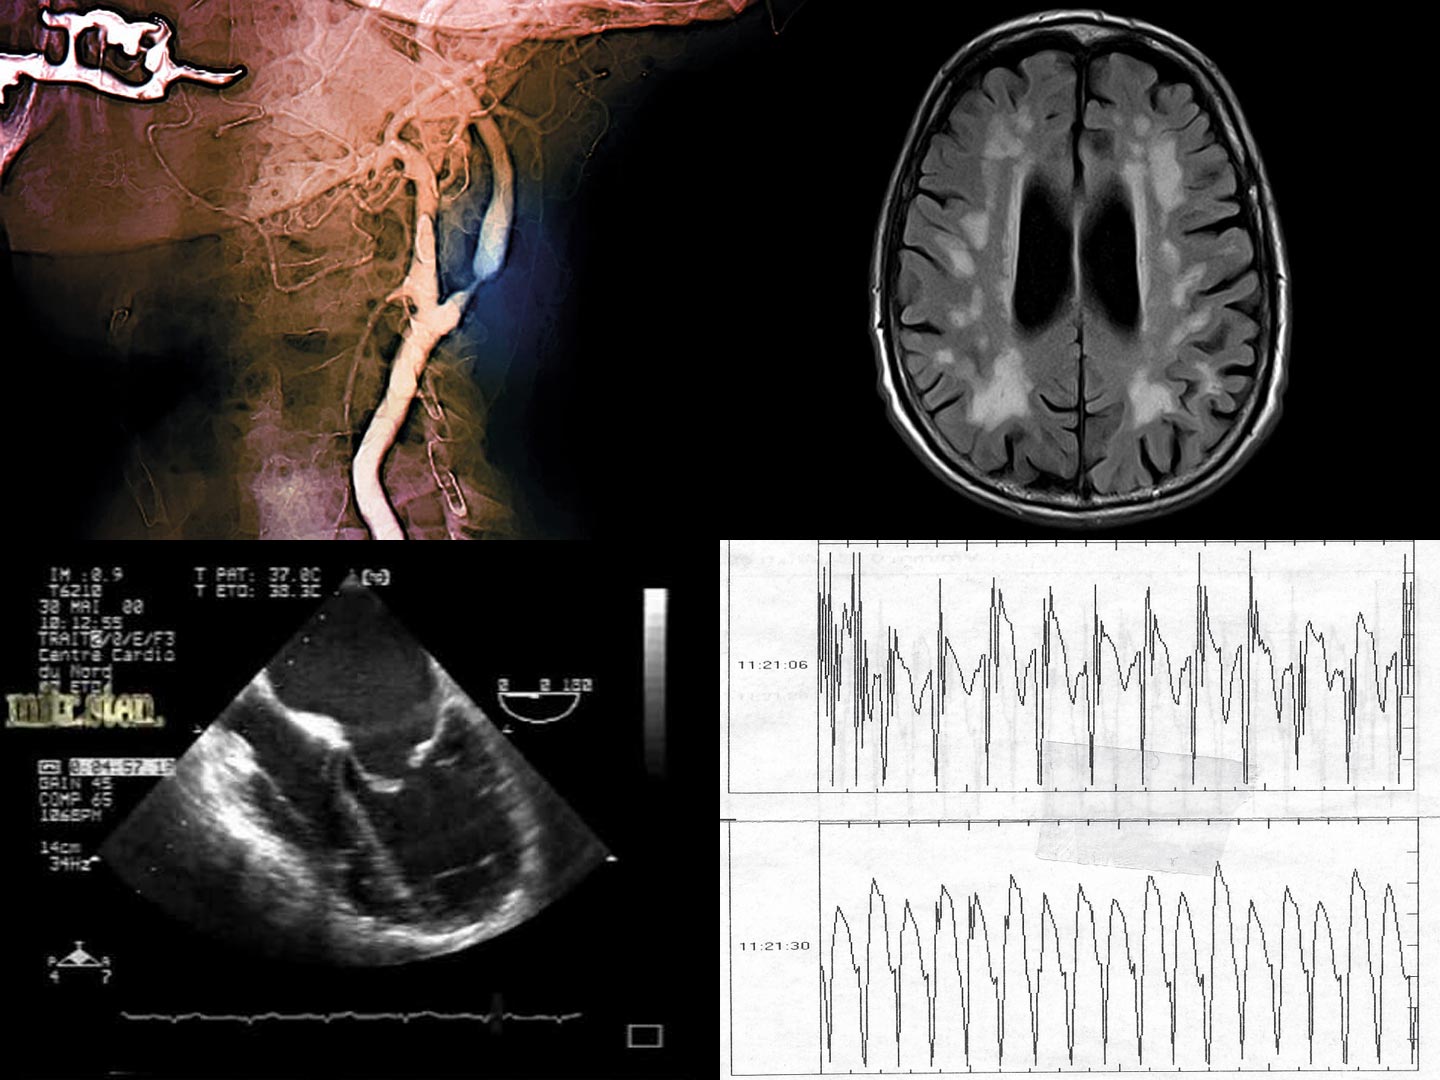

Nous sommes heureux de vous inviter à participer à notre 13e Symposium Coeur et Cerveau. Lors de cette nouvelle rencontre, nous allons aborder diverses situations cliniques, ainsi que la prise en charge reliant les affections cardiaques et cérébrovasculaires. Un certain nombre de nouveautés et divers aspects de l’imagerie en tant qu’aide au diagnostic seront présentés.